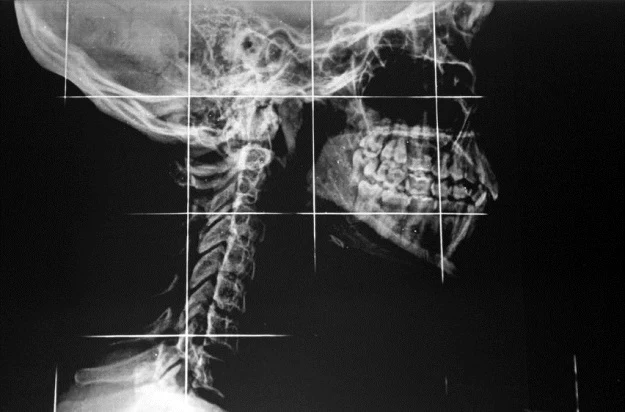

W latach 70. ubiegłego wieku naukowcy próbowali przeszczepiać głowy szympansom. 14 marca 1970 r. w wyniku 18-godzinnej operacji, neurochirurg Robert Joseph White przeszczepił głowę jednej małpy do ciała drugiej. Niestety, niewielki był z tego pożytek, bo odłączony rdzeń kręgowy nie pozwalał na kontrolę nad nowym ciałem. Niektóre organy podejmowały pracę, ale zwierzęta pozostawały sparaliżowane od szyi w dół. White powiedział wtedy, że transplantacja ludzkiej głowy powinna być możliwa na początku XXI wieku. Nie wydaje się, by znacznie się pomylił.

Mimo że eksperymenty przeszczepiania głowy prowadzone są na zwierzętach od lat 50. XX wieku, to do tej pory nie było skutecznej metody łączenia rdzeni kręgowych dawcy i biorcy. Niedawne badania naukowców z Case Western University i Cleveland Clinic na szczurach wykazały, że możliwe jest przywrócenie ogólnej kontroli nad ciałem gryzoni po osadzeniu nowej głowy. Canavero idzie krok dalej i przekonuje, że neurochirurgia rozwinęła się już wystarczająco, by planować przeprowadzanie operacji przeszczepu głowy na ludziach. W tym celu Włoch stworzył projekt Heaven/Gemini, który składa się z dwóch niemal jednocześnie przeprowadzanych faz.